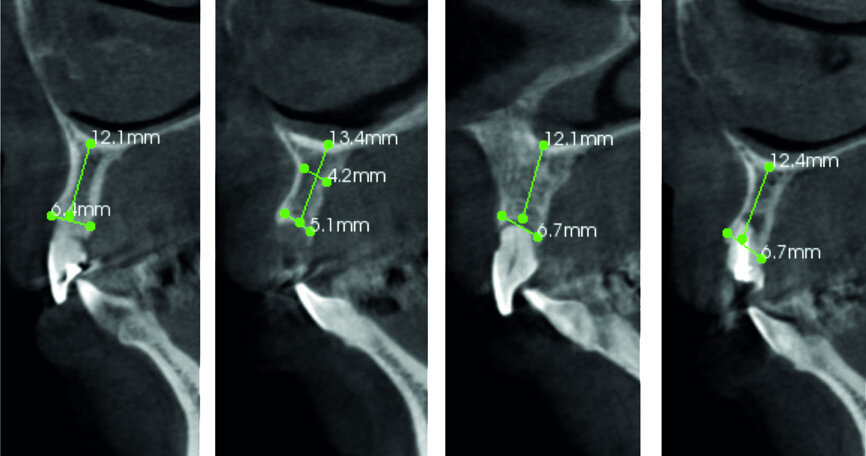

Fig. 4: Pre-op CT analysis.

Three weeks later, after a general physical check-up, implantation was begun. Usually, operation within 48 hours after tooth extraction is considered as immediate implantation, while operation within the first six weeks after tooth extraction is considered as early implantation. Therefore, in this case, implant #11 was early implantation and implant #22 immediate implantation. The preoperative CT analysis showed that the labial side of the alveolar ridge of teeth #12, 11 and 22 was deficient; thus, GBR was needed in order to obtain sufficient bone quantity.